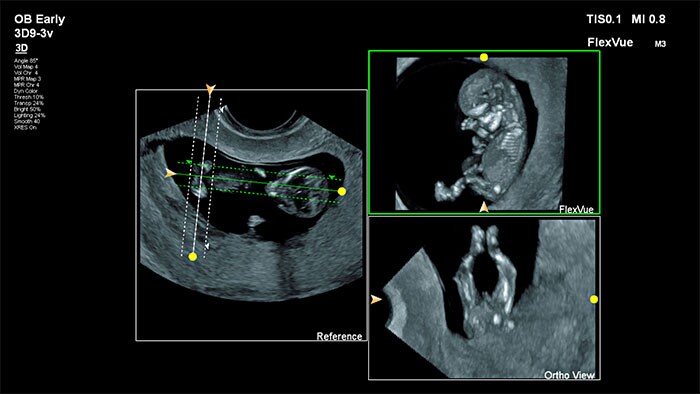

Dr. Michael Ruma uses FlexVue with Orthogonal View to enhance the diagnosis of a fetal facial cleft abnormality.

FlexVue with Orthogonal View

FlexVue with its orthogonal view are highly versatile tools that allow for easy visualization of technically difficult anatomical views from 3D volumes that are essential for diagnosis of Ob/Gyn pathology.